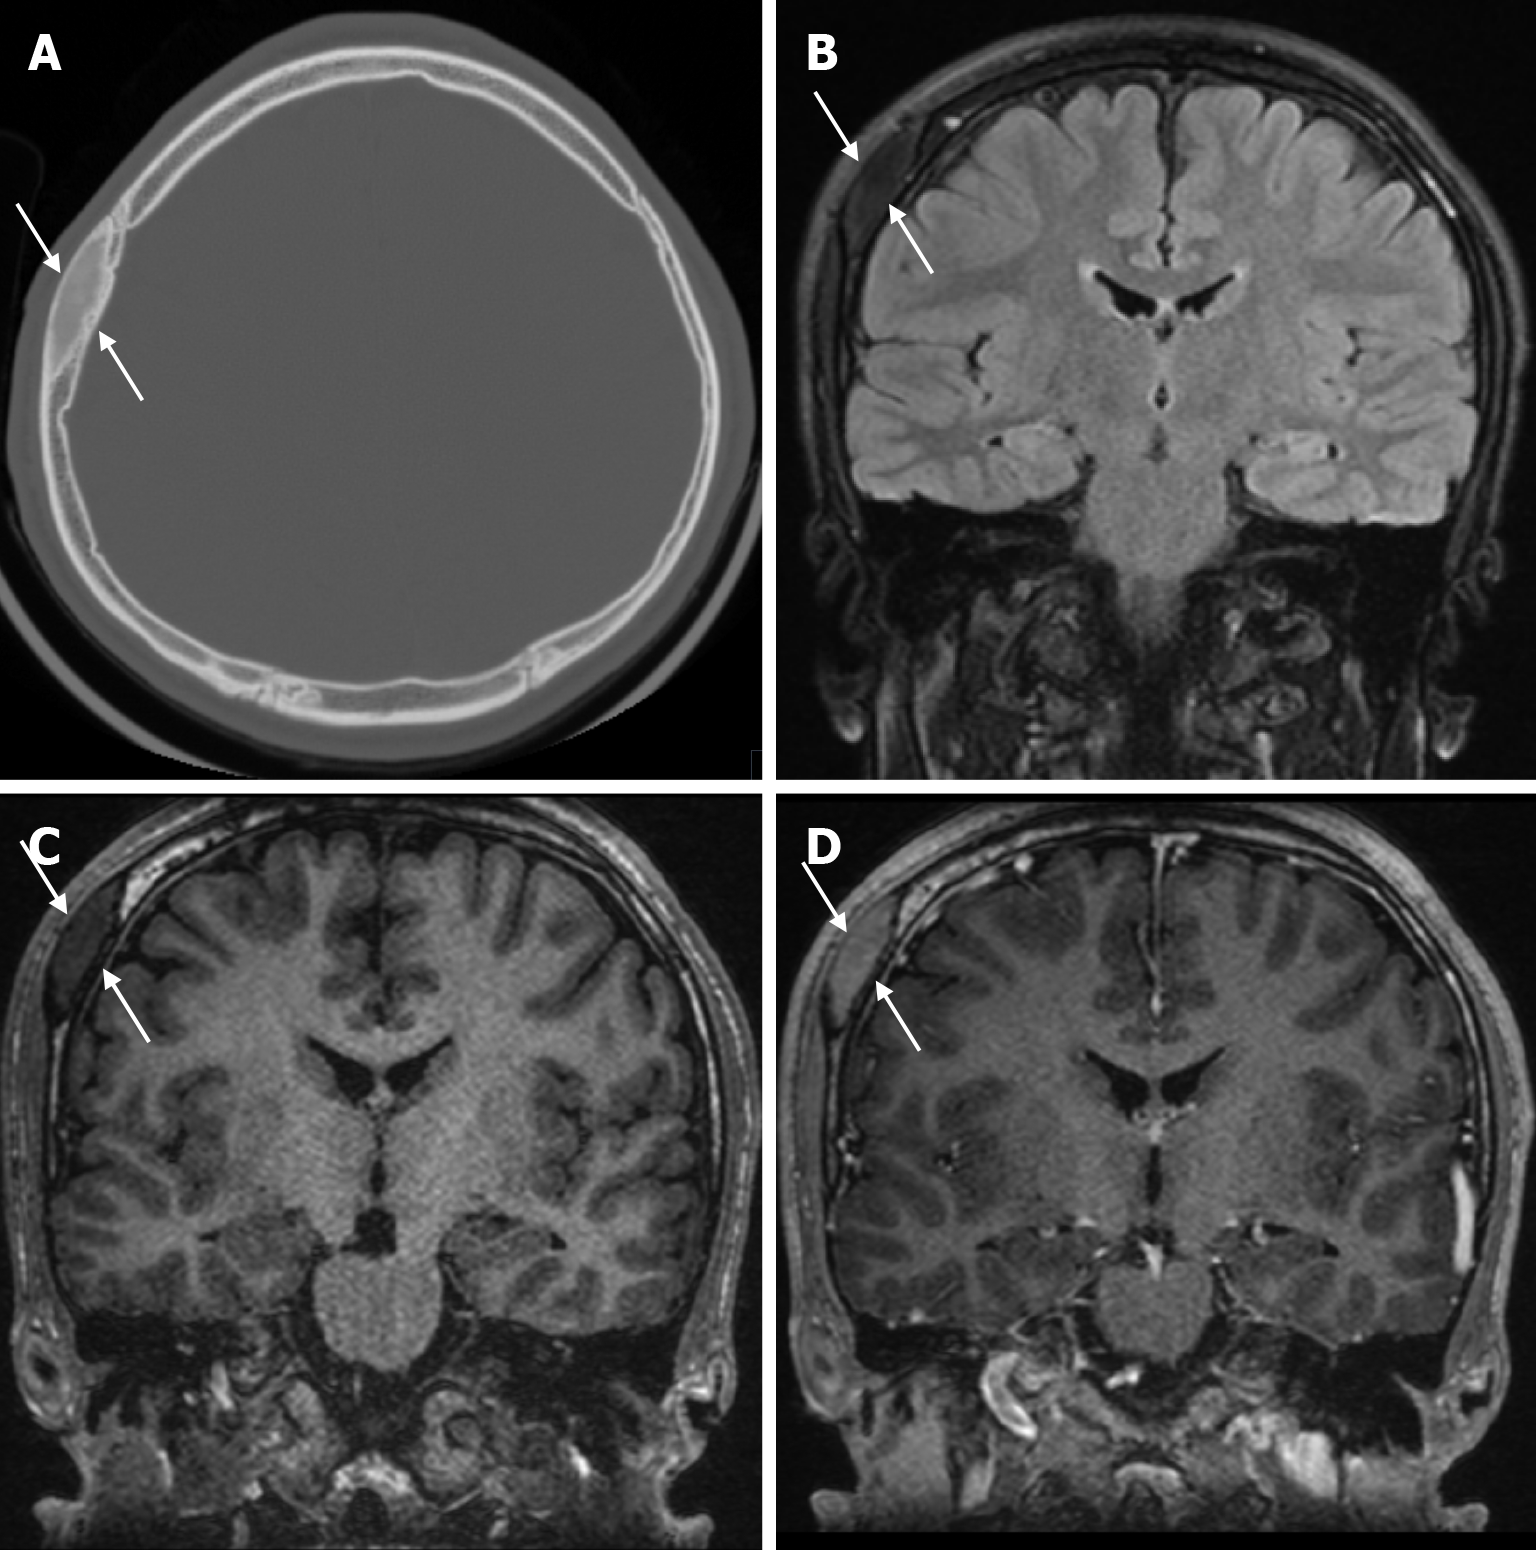

Skeletal changes in chronic anemia are due to ineffective erythropoiesis as a result of impaired haemoglobin synthesis, peripheral destruction of erythrocytes and consequently reduced erythrocyte lifespan. Radiography show massive hyperplasia of the bone marrow associated with hyperactivity of the bone marrow in response to anemia. The hair-on-end sign is seen on plain radiography of the skull, CT and MRI as long, thin vertical lines of calcified spicules perpendicular to the bone surface, appearing as upright hairs. The hair-on-end appearance of the skull is a characteristic feature of chronic haemolysis, usually seen in patients with thalassaemia (Figure 14) and sickle cell disease. The incidence of hair-on-end appearance in patients with thalassaemia is 8.3%. Although rare, the hair-on-end sign has also been described in iron deficiency anemia, sickle cell disease, cyanotic congenital heart disease, hematological malignancies and nutritional deficiencies. The appearance of these projections indicates excessive medullary erythropoiesis in patients and is rare before the age of 5 years. As the bone lesions are explained by the relationship between proliferating bone marrow and bone cortex, only hypertransfusion initiated early in life will prevent the development of the abnormality[55].

Renal osteodystrophy refers to abnormalities of bone morphology in chronic renal failure. Phosphate retention and reduced vitamin D conversion lead to hypocalcemia, which stimulates parathyroid hormone production and causes bone resorption. Therefore, factors such as secondary hyperparathyroidism and abnormal vitamin D metabolism contribute to renal osteodystrophy. Some imaging features of renal osteodystrophy overlap with those of hyperparathyroidism and rickets or osteomalacia. Skeletal findings in renal osteodystrophy include generalised demineralization, trabecular thickening, subperiosteal resorption, cortical thinning, bone cysts and pathological fractures. A diffuse increase in bone density is seen on imaging in patients with chronic renal failure. This finding is more common in the axial skeleton, which has more trabecular bone than cortical bone. Despite the increased radiodensity, the bone is structurally weak and more susceptible to stress fractures. This diffuse osteosclerosis is thought to be due to the anabolic effect of parathyroid hormone. The salt-and-pepper appearance in renal osteodystrophy (Figure 15) results from diffuse bone thickening with loss of distinction between the inner and outer tables of the skull and granular deossification due to low-density lytic foci scattered within the normal bone[9,56].

Fibrous dysplasia appears on CT as an intradiploic, expansile lesion with a characteristic ground glass matrix over most of the lesion (Figure 18). The outer table is more involved than the inner table (Figure 19). Three types have been defined according to their appearance on CT: Lytic, sclerotic and mixed (Figure 20). The more characteristic homogeneous sclerotic (ground-glass density) type is the most common. The signal and contrast enhancement properties of fibrous dysplasia lesions on MRI vary depending on the ratio of fibrous tissue and mineralized matrix within them. The homogeneous sclerotic type is the most common and the lesion typically has a low signal on T1-weighted and T2-weighted images. Signal intensity on T2-weighted images is heterogeneous and depends on the density of fibrous tissue, intralesional cellularity, and hemorrhagic or cystic components. Lesions of fibrous dysplasia with highly mineralized stroma tend to show low signal intensity on both T1-weighted and T2-weighted images, whereas lesions containing dense fibrous tissue tend to show intermediate signal intensity on T1-weighted images and high signal intensity on T2-weighted images. Contrast enhancement after gadolinium administration is also variable and not useful for diagnosis[9,49].